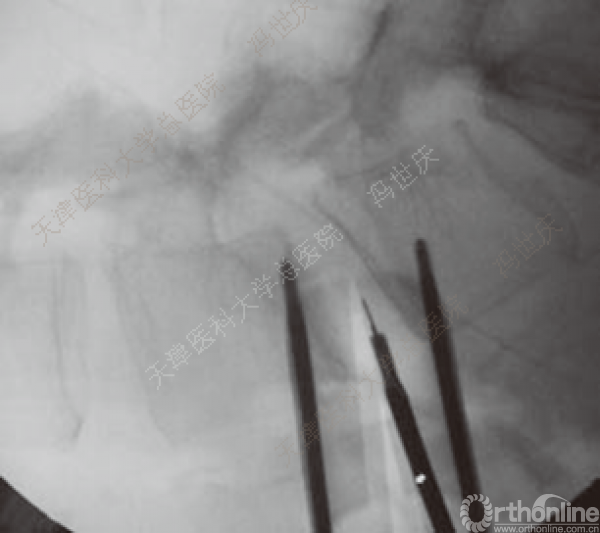

纤维环部分切除

终板全切除